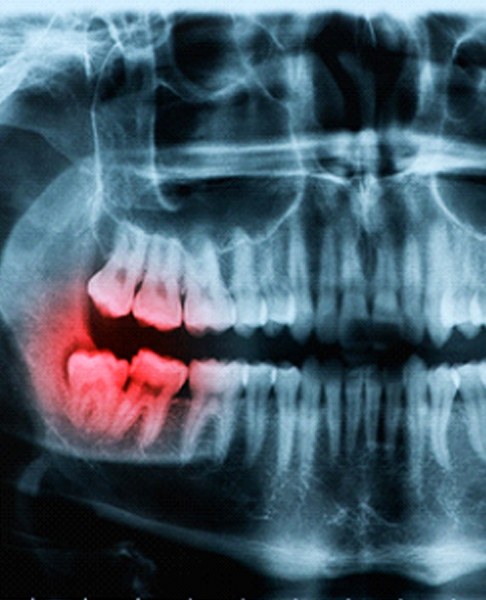

Most people have four wisdom teeth located at the very back corners of their mouths. The wisdom teeth normally erupt far later than the rest of the teeth, which means they often don’t have the room they need to grow. This causes them to become painfully impacted underneath the gums. To stop the discomfort and damage that wisdom teeth can cause, call Dr. Barnett and the rest of our periodontal team to ask about wisdom tooth extractions in Dallas.

Why Do Wisdom Teeth Need to Be Removed?

Surprisingly, not everyone has to have their wisdom teeth removed. The surgery becomes necessary if:

- The wisdom tooth fails to break through the gums all the way or at all.

- The wisdom tooth grows at an angle, damaging the teeth next to it.

- The wisdom tooth causes a significant amount of pain.

- The wisdom tooth cannot be properly brushed or flossed, increasing your risk of cavities and gum disease.

- A cyst forms around the wisdom tooth.

Keep in mind that even if you cannot see your wisdom teeth, you may still have them. An X-Ray can reveal how many you have and whether they are posing an imminent threat to your oral health.